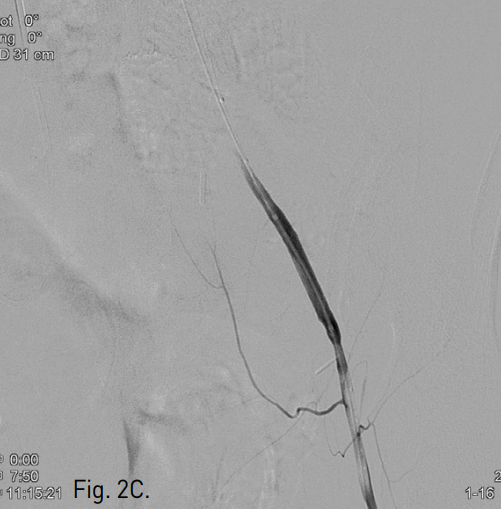

B. A radiograph shows temporary balloon tamponade (arrow) at perforation site to prevent active bleeding.